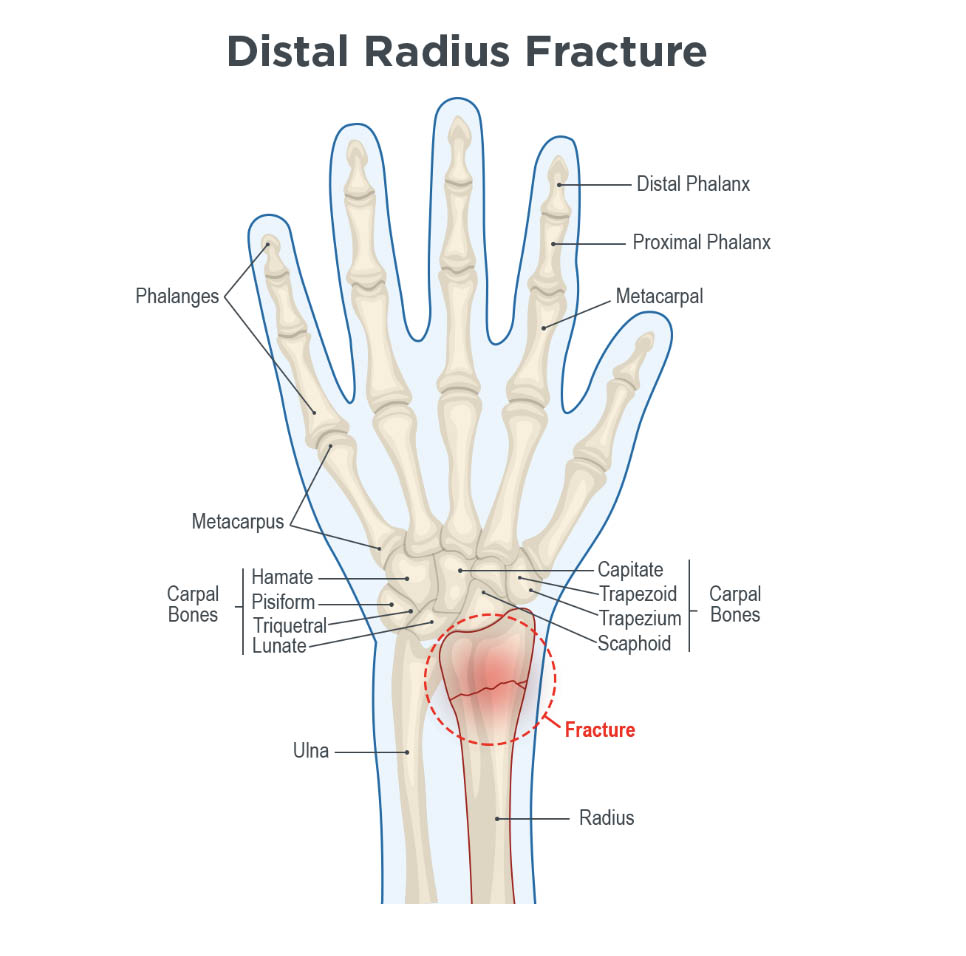

Wrist Fractures (Distal Radius Fractures) – Pro doctor

Wrist Fractures Information | Florida Orthopaedic Institute

Wrist Fractures (Distal Radius) – Hobart Orthopaedics

What Is A Wrist Fracture?

Distal radius fracture: causes, symptoms, conservative and surgical …

Distal Radius Fracture – Orthopedics – Medbullets Step 2/3